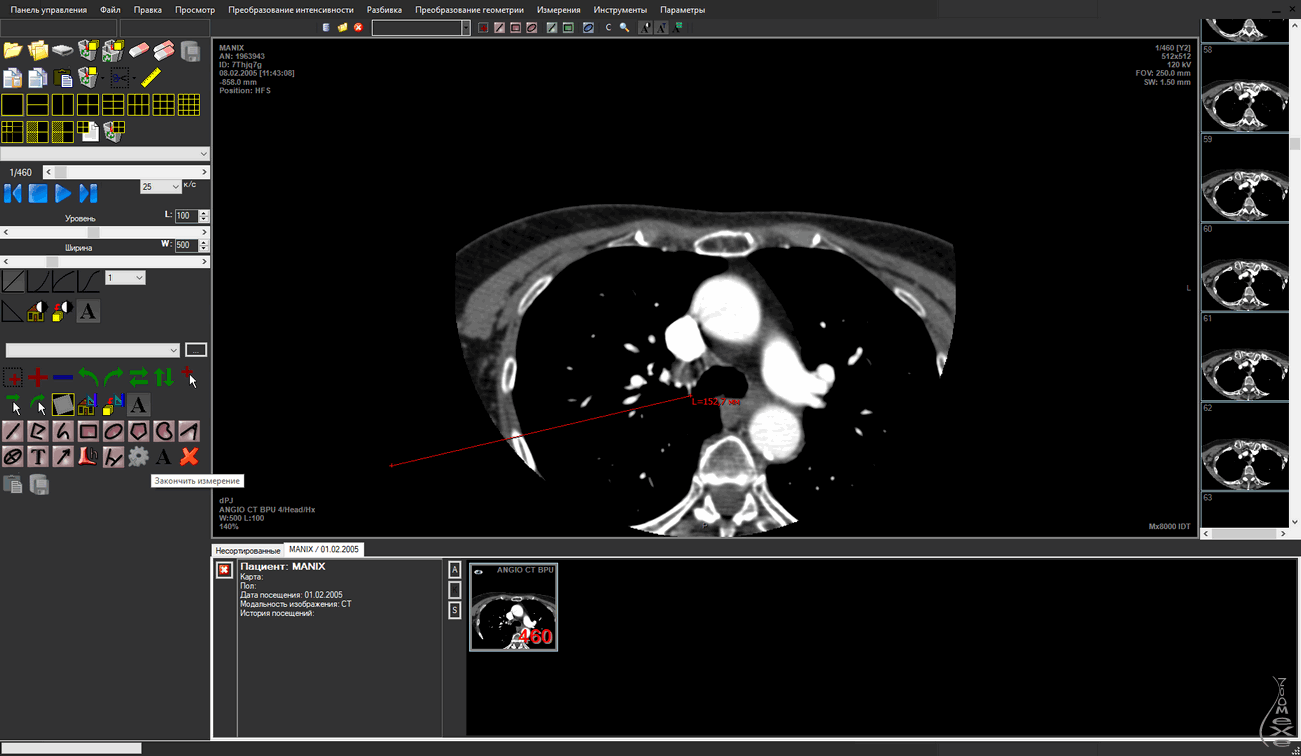

Визуальное сравнение

просмотра изображений, полученных при проведении исследований.